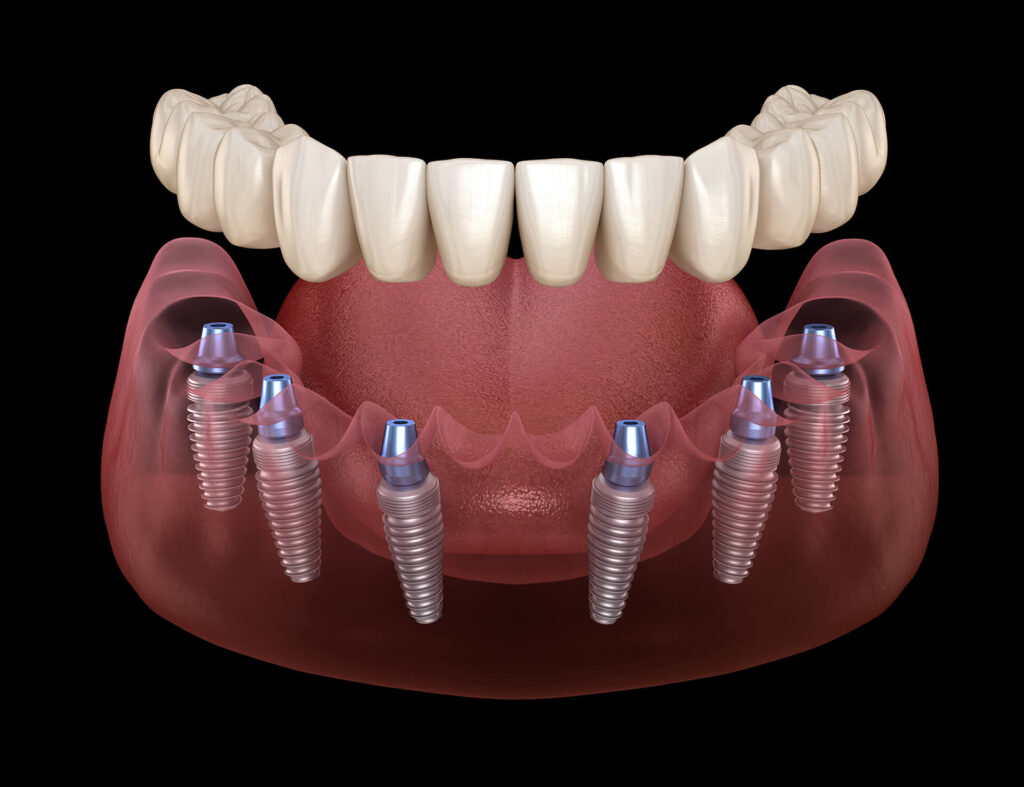

Implant-Supported Dentures: Stability and Confidence for Complete Tooth Replacement

Losing multiple teeth or an entire arch can significantly impact eating, speech, and confidence. While traditional dentures have long offered a solution, many patients struggle with instability, reduced chewing efficiency, or discomfort. Implant-supported dentures represent a modern approach, combining the removable convenience of dentures with the stability of dental implants. In Singapore, where dental practices […]